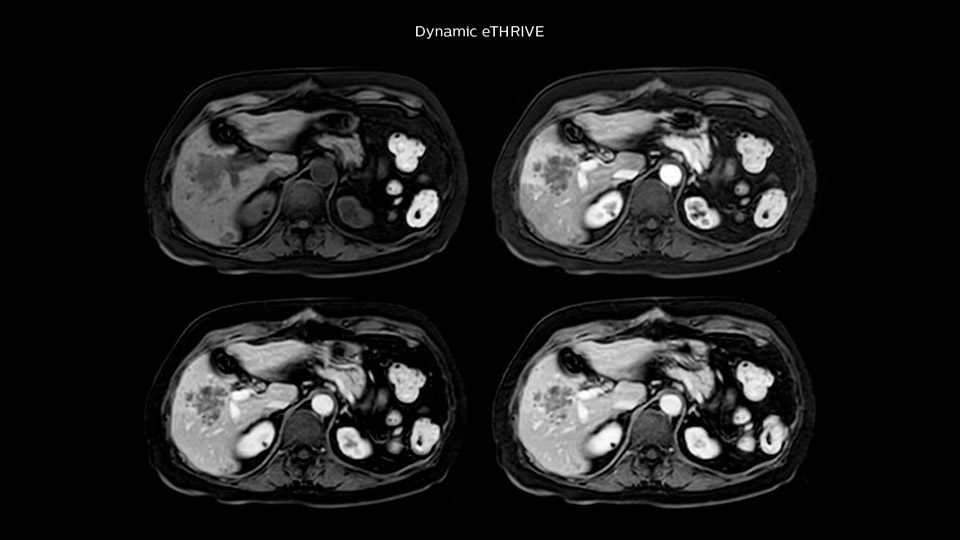

“Our liver exams are quite fast,” says Dr. Baumann. “If the patient tolerates it, we use an arms-up position to reduce the FOV and speed up the exam with dS SENSE.” “We acquire one transversal high resolution T2-weighted sequence with 3 mm slice thickness, for example for pancreas or liver lesions. Then we also add a T2 fat suppressed MultiVane XD SPIR sequence. We perform these two routinely in our liver imaging. We use high dS SENSE factors to significantly shorten scan times to 2-4 minutes, which can improve our protocol; it’s a very robust scan.” “We include mDIXON for the dynamic sequences because of the robust and homogeneous fat suppression we get with that. We had been using eTHRIVE, but we are now quite happy with mDIXON. Sometimes we use a medication to calm the bowels, to further improve the image quality.”

“We are more confident in our diagnosis if we don’t have to rescan the patient and compare it to other studies; this liver exam gives us good image quality in a faster time than the default system’s approach with arms down. That makes a difference for the patients, too. The shorter scan times, especially with the high dS SENSE factors, shorten the duration of the total examination. At the same time it’s more comfortable for the patient, to rest normally without holding the breath, just relaxing.”